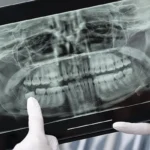

Dişlerdeki çapraşıklık, hizalanma bozuklukları ve çene yapısı problemleri hem estetik hem de sağlık açısından önemli bir konudur. Ortodonti tedavisi, bu sorunları düzeltmek için çeşitli yöntemler sunar. Günümüzde en sık tercih edilen iki yöntem ise metal teller ve şeffaf plaklardır. Peki, hangisi sizin için daha uygun? Karar vermenize yardımcı olacak detaylara birlikte bakalım.